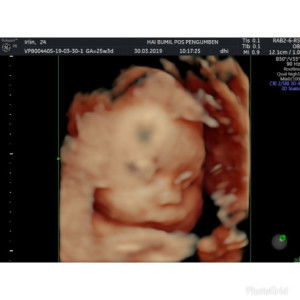

Bunda, Di usia kandungan brp minggu y, debaynya udh mulai nendang"/ akrobatik di dlm perut ibunya?. trims..

saya pas 19w bun😊